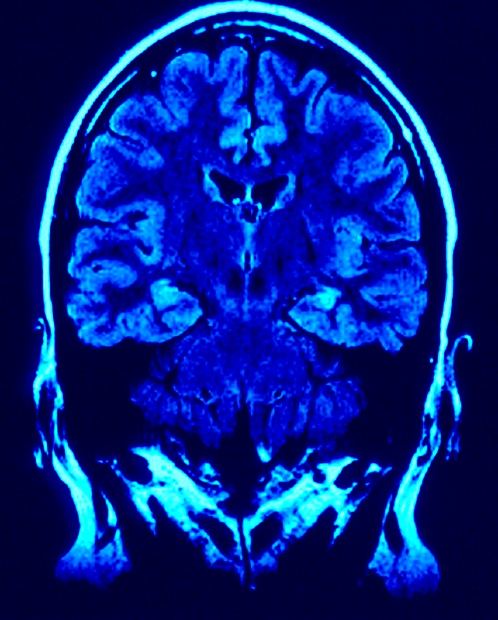

Mózg lubi niebieskie światło

Szwedzcy badacze doszli do wniosku, że fale światła niebieskiego mogą być stosowane do poprawienia funkcji poznawczych i zwiększenia poziomu energii. Ich zdaniem światło wpływa pozytywnie na mózg i poprawia ogólne funkcje psychomotoryczne oraz czujność.

Wcześniejsze analizy sugerowały, że ekspozycja światła niebieskiego, zwłaszcza przed pójściem spać, może zaburzać rytm snu, m.in. poprzez ingerowanie w produkcję hormonów. Teraz badacze są zdania, iż światło pozytywnie wpływa na mózg i jego funkcje motoryczne oraz pomaga w poprawie pamięci, jak i sprzyja szybszemu reagowaniu na bodźce. Niemieccy lekarze opracowali nawet metodę, która wykorzystuje światło w leczeniu przewlekłego bólu. Planowane też jest użycie go do stymulowania oraz poprawy aktywności mózgu u osób niewidomych.